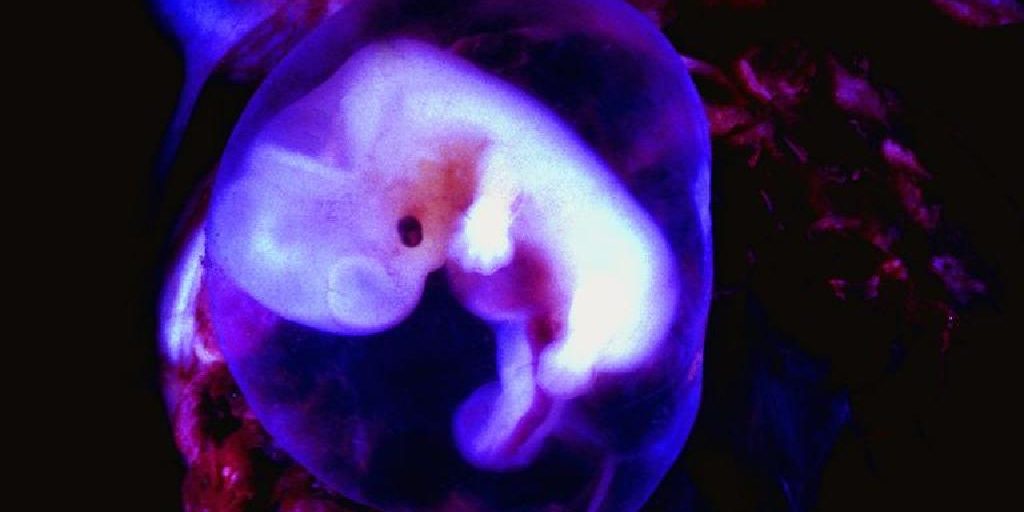

Причински абортус се случува во 10-15% од сите бремености, додека пак рекурентен губиток на бременост настанува кај 1% од жените. Ризикот за повторување не се зголемува по еден губиток на бременост. По два губитоци ризикот е 17-35%, а по три е 25-49%. Речиси 75% од губитоците на бременост се случуваат пред 13-та гестациска недела, додека пак 77% од губитоците на бременост се blighted ovum бремености.

Два најважни ризик фактори се возраста на жената и бројот на претходни губитоци на бременоста. Во повеќето случаи, причината не е позната, сепак, најверојатно постојат ризик фактори, асоцирани со развојот на фетусот и плацентацијата во позадина.